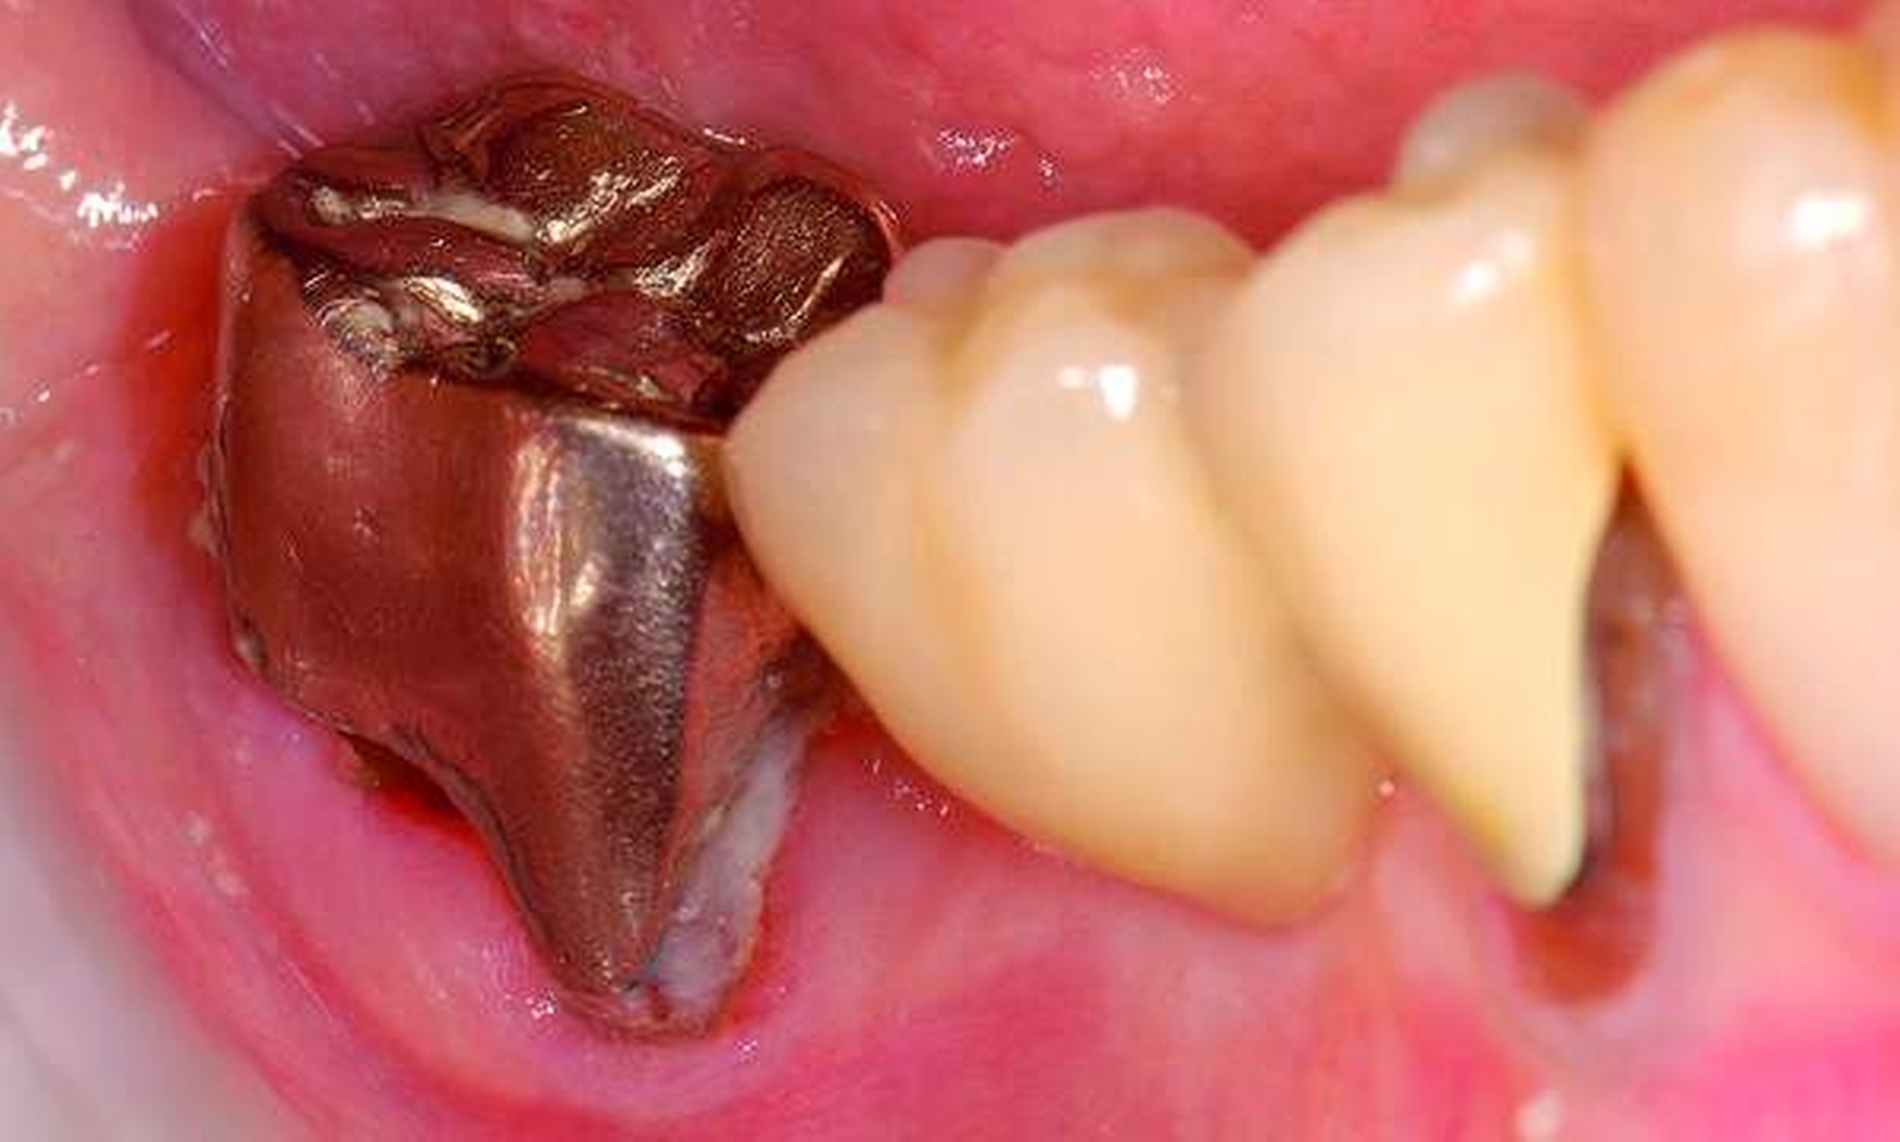

Abbildung 4: Anliegen eines 76,5-jährigen Patienten (Anfrage per E-Mail). Zitat: „Mich plagt eine … Entzündung des Mundraums, die auch das Zahnfleisch meiner Zahnstummel angreift, weshalb ich nur noch Breiartiges zu essen vermag. Ein Angsthase wie ich geht zum Zahnarzt NUR unter dem Eindruck akuter Schmerzen!“

Damit wird die Hygienefähigkeit zumindest partiell verbessert und Spielraum für künftige Planungen und Vorgehensweisen unter besseren Bedingungen belassen. Das Procedere ist in den Abbildungen 4 und 5 beschrieben. Bei dem in Abbildung 4 vorgestellten Patienten lag eine Oralphobie im Seniorenalter vor. Die Verlaufsbeschreibung macht deutlich, dass selbst im fortgeschrittenen Alter eine Adaptation an zahnärztliche Interventionen im Einzelfall noch möglich ist.

4. Vorgehen bei frakturierten Zahnkronen/Wurzelresten

Üblicherweise werden frakturierte Zahnkronen beziehungsweise Wurzelreste restaurativ wieder aufgebaut oder es erfolgt eine Extraktion. Im Seniorenalter erscheint es hingegen manchmal als Kompromissmaßnahme vertretbar, Wurzelreste vorerst zu belassen und etwa mit adhäsiv eingebrachtem Komposit knapp über Gingivahöhe abzudecken. Dies bietet sich vor allem dann an, wenn die Wurzelkanäle bereits obliteriert und endodontische Interventionen nicht erforderlich sind (Tabelle 4) [Staehle et al., 2017].